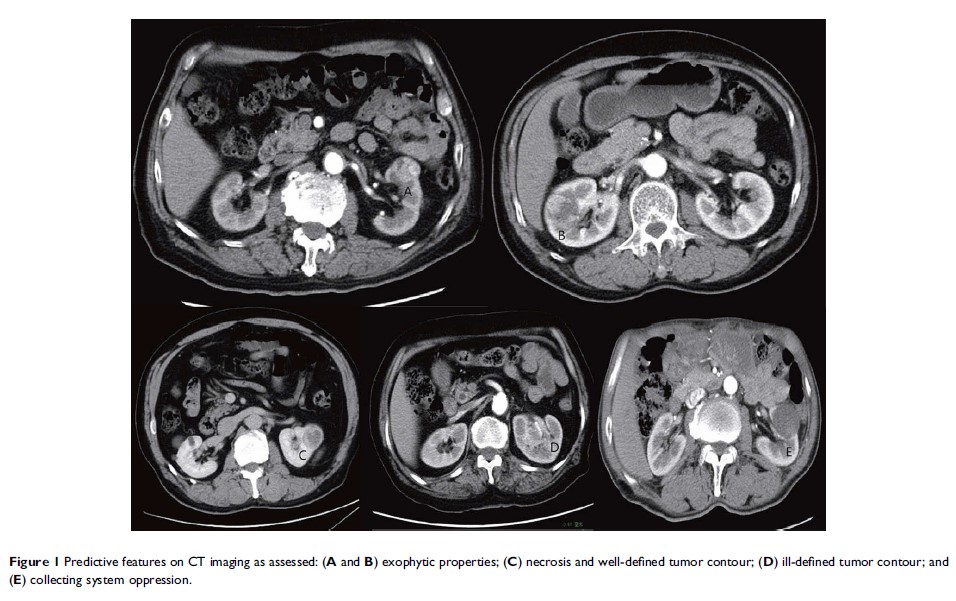

对用于预测不良的高级别肾脏小肿块的 CT 成像术前列线图的开发和验证